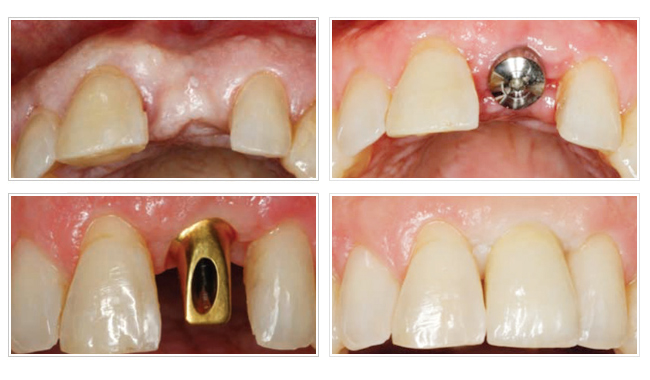

3D齒雕植牙

CEREC 3D 齒雕是目前唯一可臨床使用的全瓷牙高科技設備,能夠一個診次就為病患完成美觀的全瓷修復體,病患可以不需要戴上臨時牙套,不需要多次約診與等待一周,牙醫師就能將專業與科技作搭配,輕鬆完成高品質的全瓷修復治療。CEREC 3D 齒雕擁有當代的電腦運算科技,精密的光學影像擷取技術,準確的研磨製造程序,與時尚精練的外觀工業設計,能夠完美的整合在診所的環境與治療流程中。

CEREC 3D 齒雕全瓷冠屬於一體成型的結構設計,使用的是在全球擁有專利的創新牙科瓷材:IPSe.maxCAD 瓷塊(LithumDIsilicate,二矽酸鋰)製作,能夠提供比一般的技工堆燒瓷材三倍以上的彎曲強度。IPSe.maxCAD瓷塊的製造過程是在工廠中進行全自動的壓鑄與製造,擁有精密穩定的高品質保證,並且瓷塊有多種的比色與透光度的設計,完全符合各種臨床全瓷修復體的製作需求。

紐約大學牙科學院(NYU)的研究人員對於全瓷冠強度有了最新的研究發表,研究人員將兩種不同製作結構的全瓷冠,透過口腔運動模擬器去做咬合壓力模擬的反覆周期測試,結果顯示一體成型的全瓷冠結構,相較於內冠堆瓷的全瓷冠結構而言,更能承受較高的模擬咬合壓力測試,證實為高強度且耐用的全瓷冠材料,因此CEREC 3D 齒雕植牙不只能快速的完成植牙手術,再搭配全瓷牙冠,讓新的牙齒強度更高也更耐用。